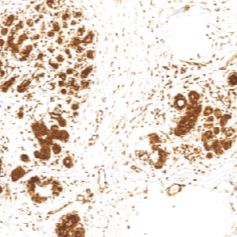

O⁶甲基鸟昔-DNA-甲基转移酶(MGMT)是一种DNA修复蛋白,正常组织常有表达,而肿瘤组织表达低,可能与该基因的甲基化有关,同时也是继发性耐药的一种标记,主要用于结肠癌、星型细胞瘤等各种恶性肿瘤的研究

- 阳性部位:胞核,胞质

- 适用组织:石蜡切片

- 预处理:热修复